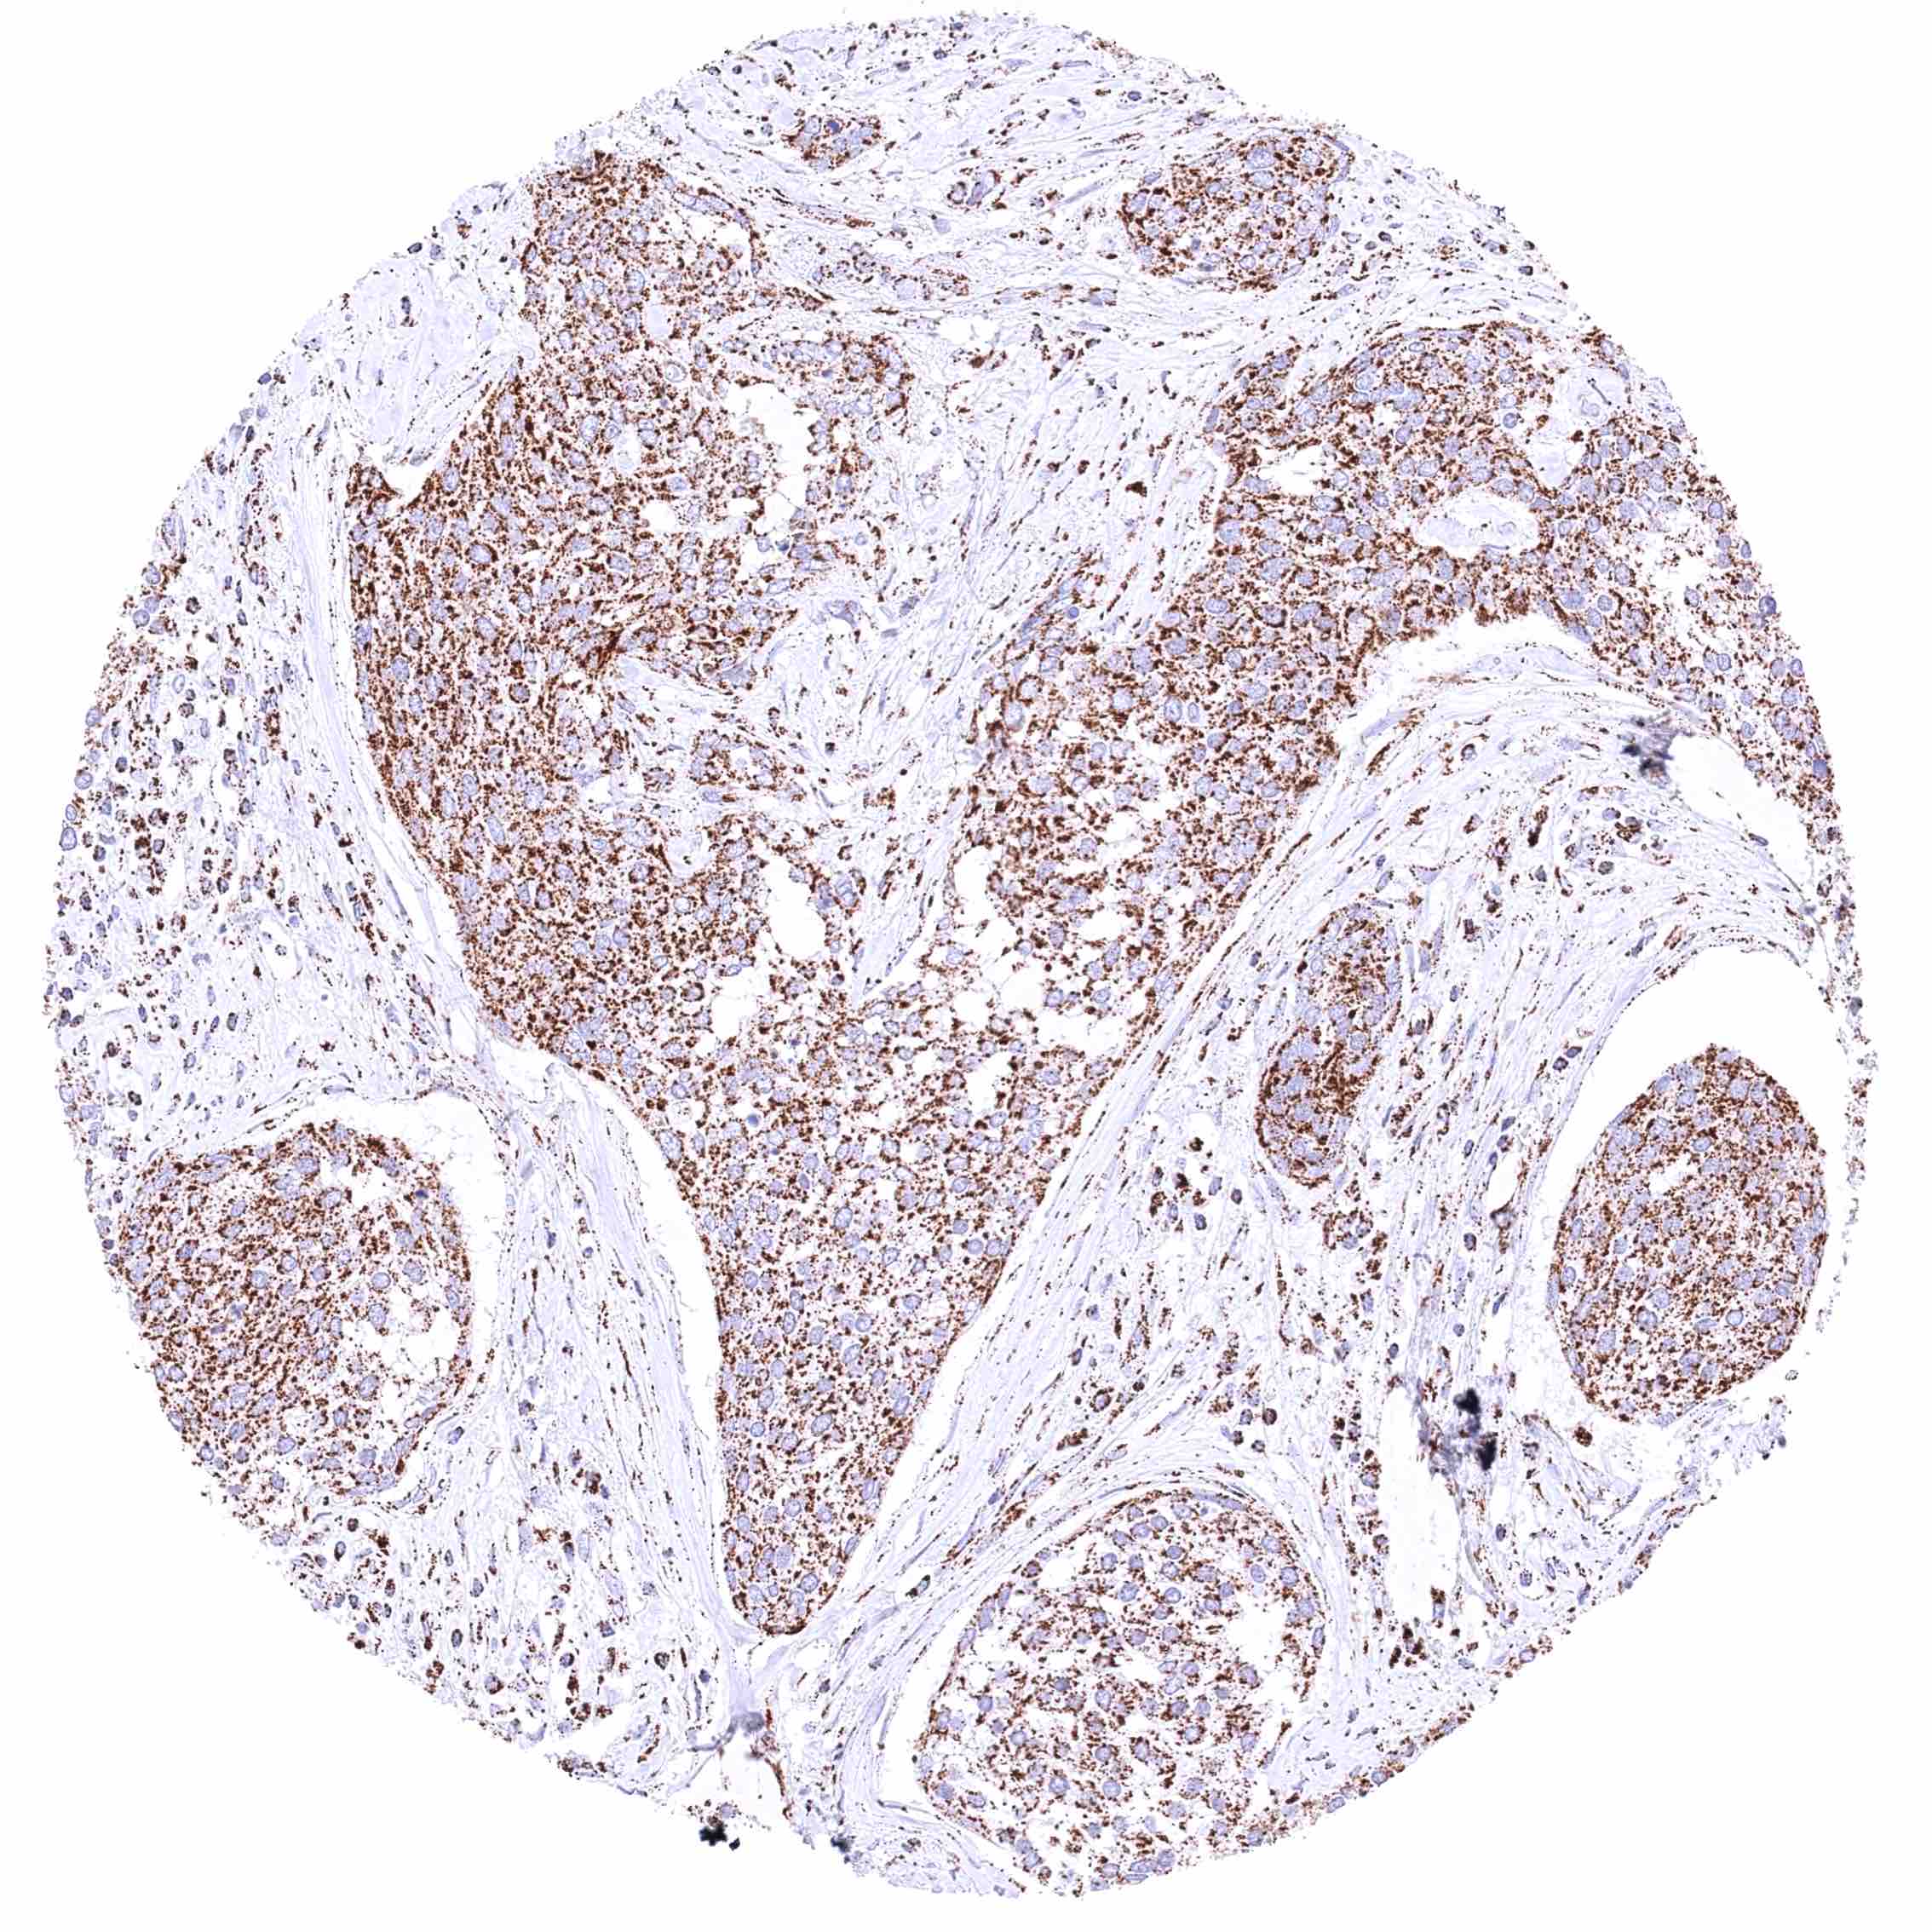

Lymph node – B-CLL with moderate cytoplasmic ATP5J immunostaining of tumor cells.